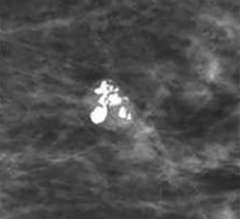

Fine Pleomorphic Calcifications

Fine pleomorphic calcifications: calcifications of different shapes and sizes, with a size between 0.5 and 1.0 mm, smaller than coarse heterogeneous calcifications. These are considered a 4B category finding.